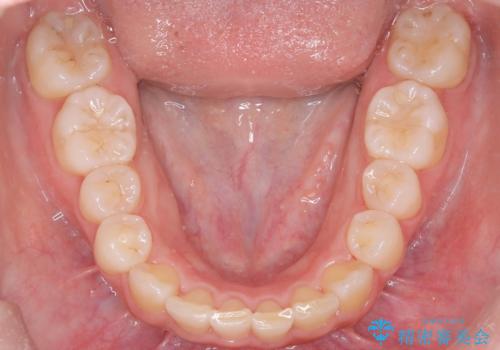

- 歯のデコボコ(叢生)を気にされて来院されました。精密な検査の結果、中等度の叢生と診断。患者様のご希望に合わせ、透明で目立ちにくい**インビザライン(マウスピース矯正)**による治療計画を立案しました。歯を抜かずに、歯列弓(歯が並ぶアーチ)を少しずつ拡大することで、歯が並ぶスペースを確保し、叢生を改善することを目指します。

今回の矯正治療では、透明なマウスピース型の装置インビザラインを使用しました。この装置は目立ちにくく、取り外しが可能なため、食事や歯磨きも普段通りに行えます。治療は、緻密に計算された治療計画に基づき、段階的に作製されたマウスピースを交換していくことで、歯列弓全体を徐々に広げていきました。この歯列弓の拡大により、不足していたスペースを確保し、歯のデコボコを効果的に解消。抜歯することなく、整った美しい歯並びと良好な咬み合わせを獲得していただけました。